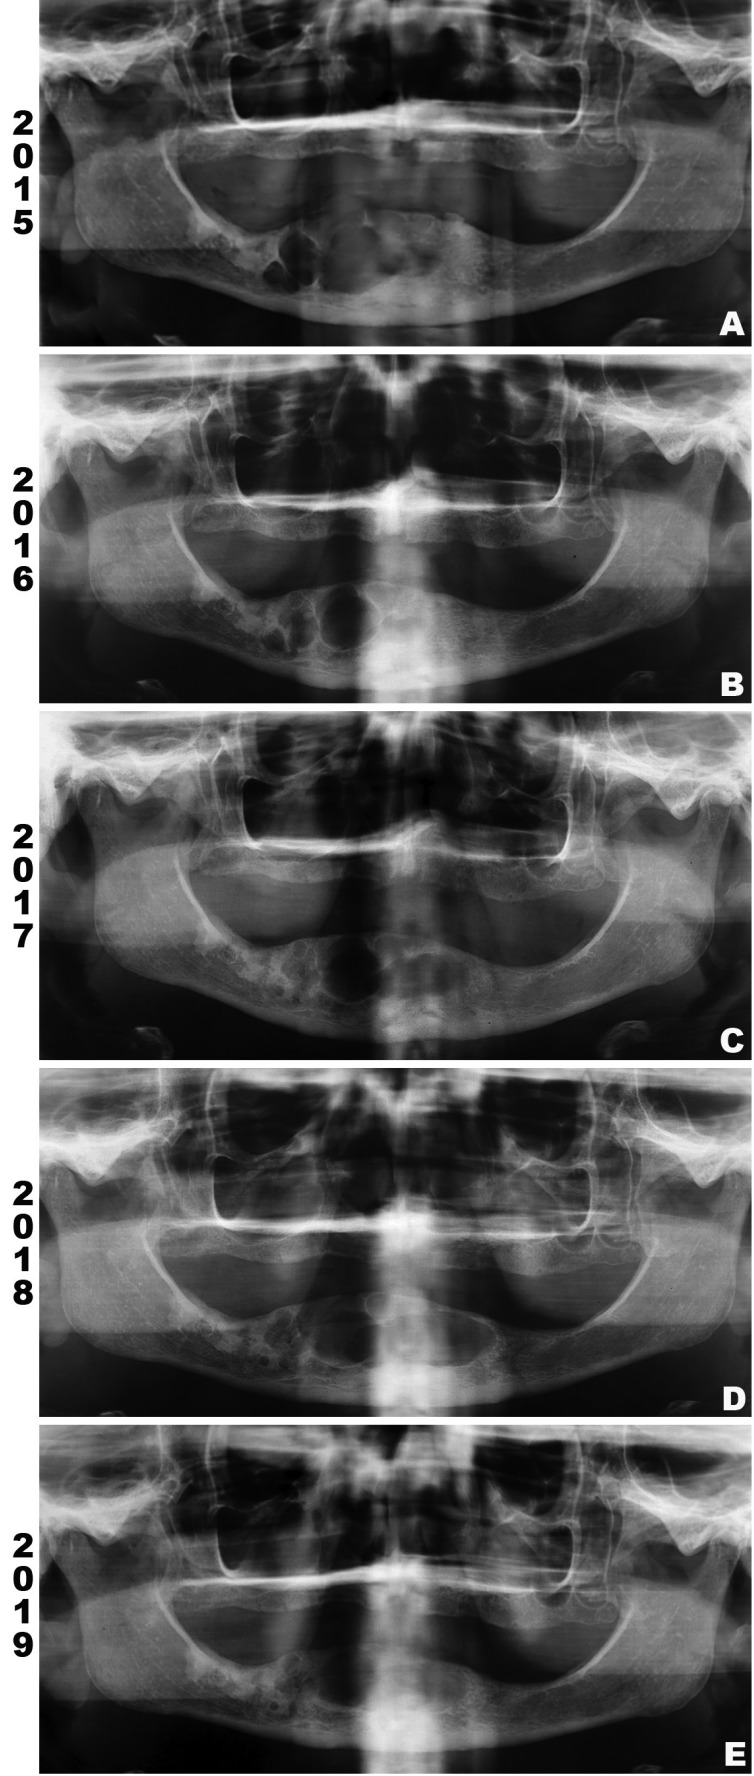

Medical history of the patient revealed systemic arterial hypertension controlled by oral drugs. A panoramic radiograph from 2015 revealed a large, multilocular, well-defined radiolucent lesion extending from the region of left mandibular lateral incisor to right mandibular first molar teeth, with no evidence of cortical perforation (Fig. 1a). At this moment, it was proposed a conservative treatment with intralesional injection of corticosteroids to decrease the size of the lesion.

Figure 1.

Panoramic radiograph (PR). (A) PR taken in 2015 showing a large, multilocular, well-defined radiolucent lesion extending from the region of left mandibular lateral incisor to right mandibular first molar teeth. (B) PR taken in 2016 indicating decreases of the lesion on right posterior region of mandible. (C and D) PR from 2017 and 2018, respectively, revealing increase of osteolytic component on anterior region of mandible, extending to the left side. (E) PR from 2019 shows increased radiopacity of the lesion, indicating bone repair.

During 18 months, the patient received monthly 1 ml of Dexamethasone (4mg/ml) applied intralesionally. To reassess the response to the treatment, panoramic radiographs were performed in Dec/2016 (Fig. 1b), Aug/2017 (Fig. 1c) and Feb/2018 (Fig. 1d). In the first radiography, the lesion decreased, specially in the right posterior region of mandible. However, the two last exams revealed an increase of the osteolytic component of the lesion in the anterior region of mandible, extending to the left side and causing an expansion of cortical bone on intraoral clinical examination.

The last radiography was taken in May 2019 (Fig. 1e) and revealed decreasement of the lesion, indicating bone repair. Regular follow up has not shown recurrence after 10 months of the surgical treatment.